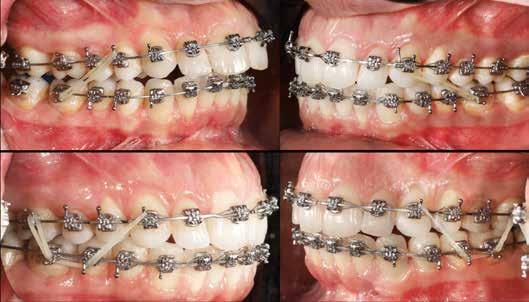

A kezelést Pitts-21-es fogszabályozó készülék alkalmazásával végeztük el. A felső fogíven mosolyvonal beállító esztétikai (Smile Arc Protection - SAP), az alsó fogíven a Spee görbe kiegyenlítését szolgáló funkcionális bracket pozicionálást

alkalmaztunk. Előbbi elengedhetetlen a szép, íves mosolyvonal kialakításához, utóbbi pedig az alsó fogsor mezializálásához, és így az első osztályú sagittális okklúzió kialakításához. Az alsó metszők torlódásának feloldására tolórugókat alkalmaztunk az első hónapban (8. kép)

A protokollok szerves része a mesterséges harapásemelés, melynek segítségével – mintegy kivéve a rágóerők fogmozgatásokat akadályozó hatását – segítjük fogszabályozó rendszer működését. Ezek a ragasztásnál az alsó 7-esekre, majd később a felső 4-esekre kerültek (9. kép).

A harapást beállító elasztikus gumihúzásokat, mint minden kezelésnél, ebben az esetben is folyamatosan, az egész ke-

zelés alatt 24 órában (étkezések kivételével) viselte a páciens. Segítségükkel történt az alsó fogsor mezializálása, és a harapásemelésben is fontos a szerepük a disztálharapás korrekciója során. Az utolsó hónapokban az okklúziós finomítások is részben a segítségükkel történnek az ívhajlítások mellett (10. kép).

A fogkontúrálás és az interproximális redukció alkalmazásával a mikroesztétikai részletek tökéletesítése is megtörtént (11. kép) A kezelés mindössze 16 hónapig tartott, megtörtént a rágófunkció helyreállítása, és az esztétikai végeredmény sokéves várakozás után valóban fordulópontot jelentett páciensünk életében (12-14. képek).